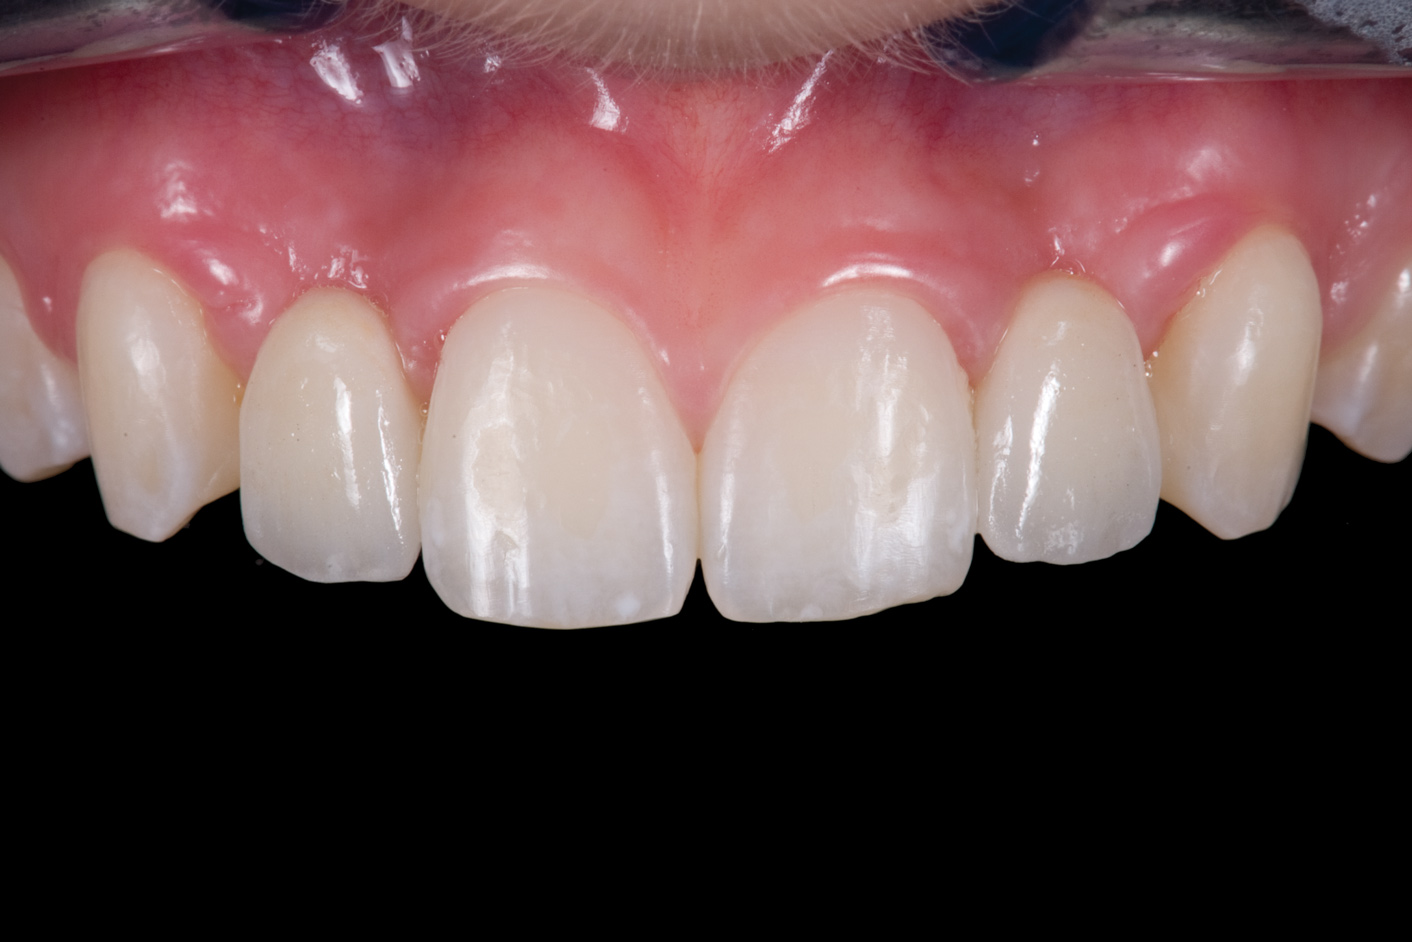

Fig 3. After resin-based composite bonding of the three incisors.

Figure 3

Fig 4. Double-wing metal resin-bonded (Maryland) bridge replacing the right lateral incisor (facial view).

Figure 4